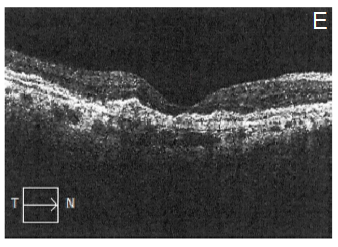

After explaining the nature of the disease, its natural course, and the alternative treatment modalities, the patient gave informed consent to this novel treatment approach. Topical antibiotics were administrated 4 times a day for 1 day before the treatment, and 5 days after it. The procedure was performed under sterile conditions in the operating room. The patient received an intravitreal injection (100µL) of etamsylate (Dycinone®, Sanofi-Aventis, Paris, France) according to the international guidelines for intravitreal injections.11 No ocular side effects were observed upon administration of etamsylate or along the following days. The intraocular pressure remained normal. At baseline, anterior slit-lamp examination was unremarkable. Posterior segment fundoscopy was striking for SMH: it had a thickness capable of inducing significant elevation of the neurosensory retina, which completely obscured the underlying choroidal pattern at biomicroscopy examination (Figure 1A). Two weeks after the treatment, colour fundoscopy revealed a partial resolution of SMH that allowed to visualize a CNVM (Figure 1B) which became imperceptible 4 weeks after treatment (Figure 1C). Furthermore, at the last post-treatment visit (8 weeks) fundoscopy revealed a complete clearance of blood and resolution of soft drusen (Figure 1D), which suggests remodelling and regeneration after the etamsylate treatment. Furthermore, corresponding OCT scans showed great improvement with absorption of the haemorrhage. Central macular thickness (CMT) was 277µm (Figure 1E), and visual acuity became 0.40.

Figure 1 Efficacy of etamsylate in the natural history of submacular haemorrhage and choroidal neovascular membrane in a patient with age-related macular degeneration.

Pre-treatment fundus photo (A) Post-treatment fundoscopy after 2. (B) 4 (C) and 8 (D) weeks. E shows a horizontal optical coherence tomography scan corresponding to the 8 weeks after treatment visit. Note the total clearance of subretinal and retinal haemorrhage without scar formation and clearance of drusen.